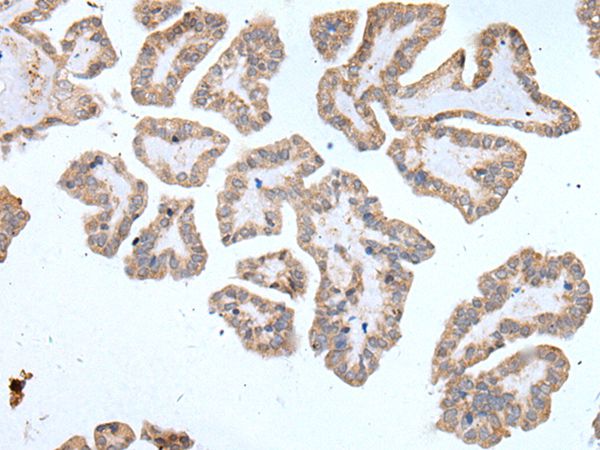

The image on the left is immunohistochemistry of paraffin-embedded Human thyroid cancer tissue using ABCD1 Antibody at dilution 1/100, on the right is treated with synthetic peptide. (Original magnification: x200)

The image on the left is immunohistochemistry of paraffin-embedded Human tonsil tissue using ABCD1 Antibody at dilution 1/100, on the right is treated with synthetic peptide. (Original magnification: x200)